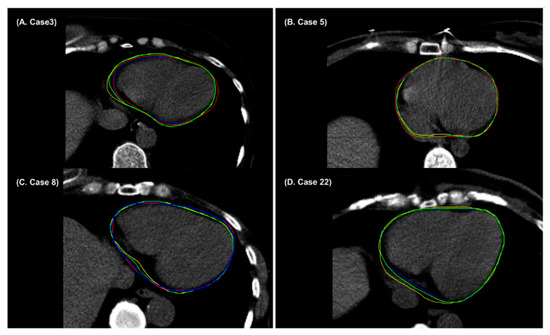

3. Results